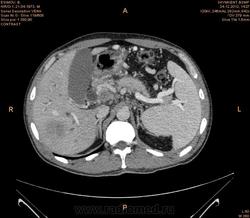

Предварительно образование головки ПЖ, и в печени. Что с ферментами?

на операций рак головки подж.железы с метастазир. печень.

инфильтрация тут нисходящей 12 перст кишки , расширенного холедох,расширенный вирсунгов проток ,нижная граница очень близко прилежит к нижней полой вене с правой почечной веной ,но четко визуализирутся передний листок фасции Героты(нельзя исключить ее инфильтрацию), инфильтрация конгломератом увеличенных лимфатических узлов ворот печени портальной вены с варикозным расширением вен, на вышележащий срезах четко определяются верхняя брыжеечная вена и артерия ,не хватает срезов для полной визуализации(помогли бы мпр),инфильтрирована восходящая ободочная кишка,конгломерат лимфат узлов за головкой поджелудочной железы в виде гиподенсивного участка вытянутой формы , ,мтс в печень,парааортальные